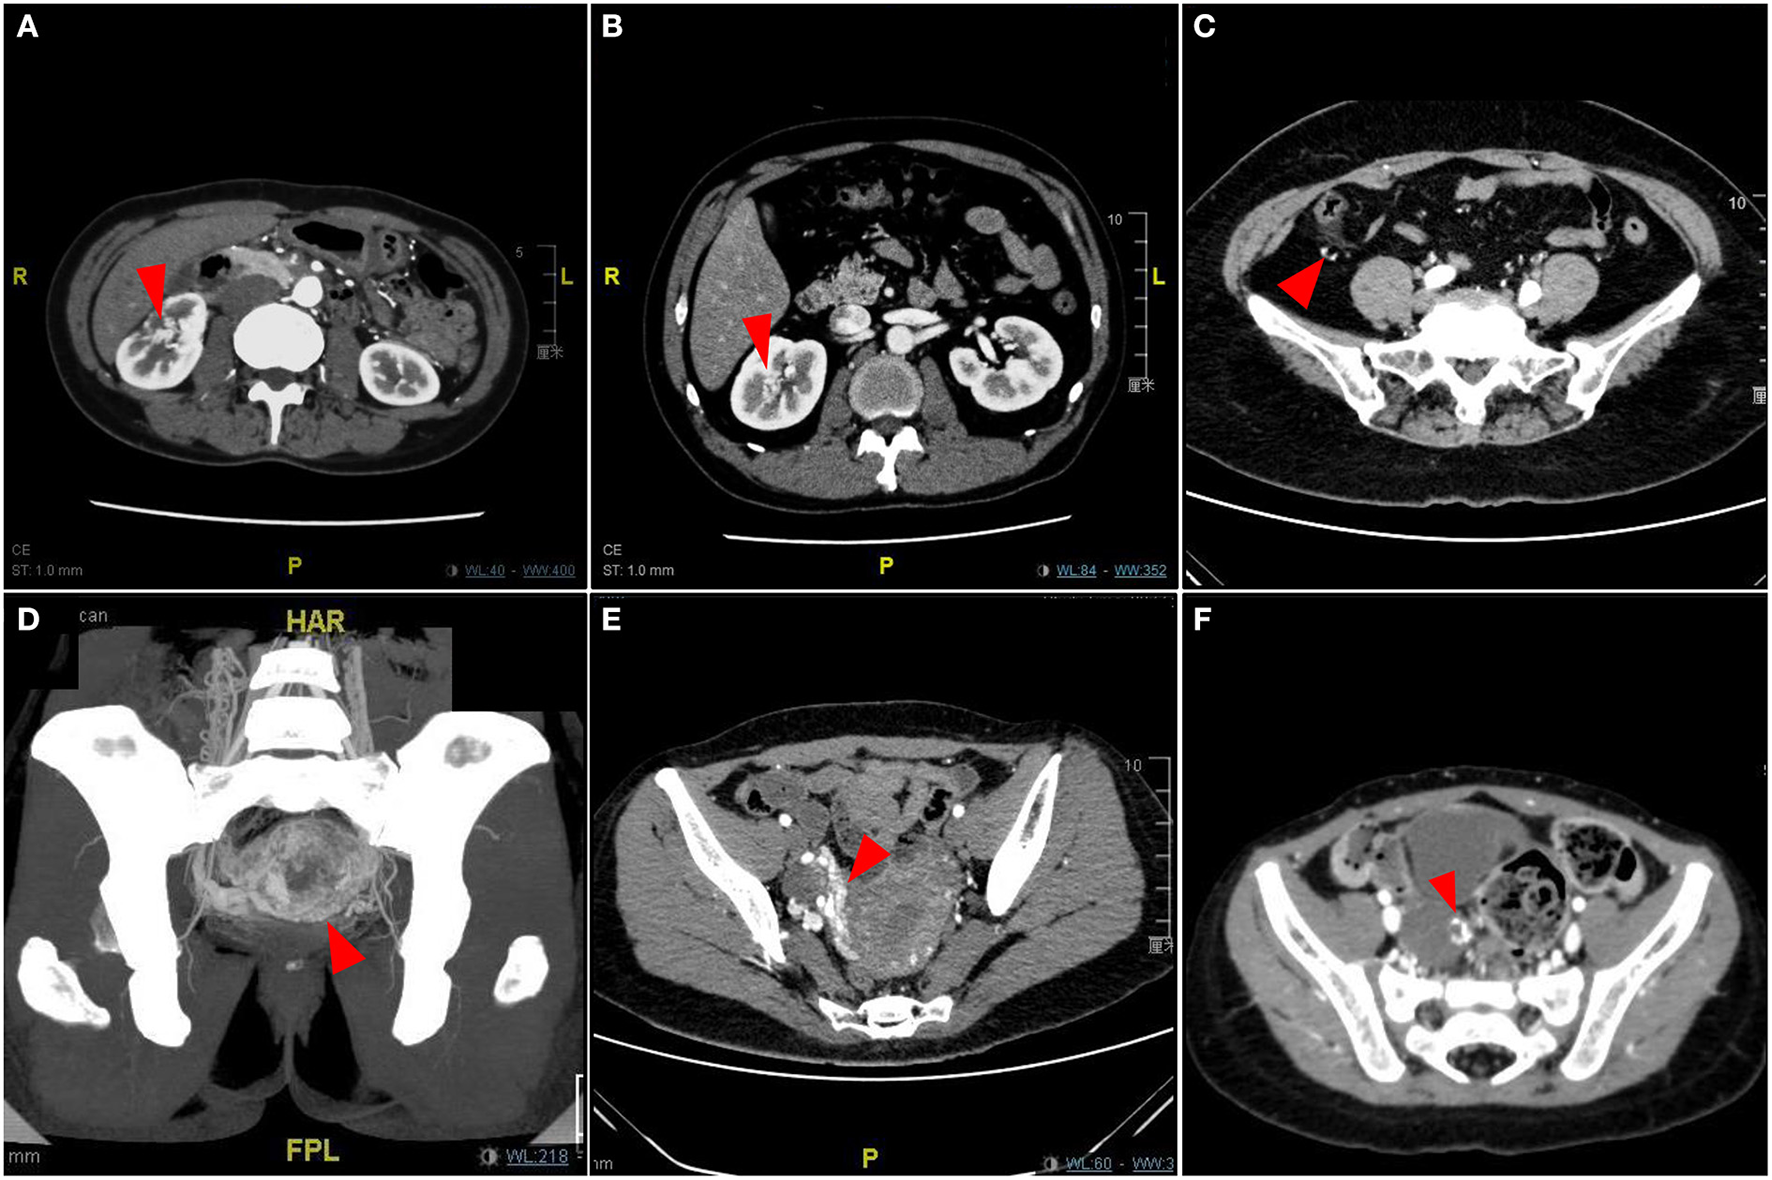

We classified the pAVM that primarily occurred in the visceral organs as Type III, which is an extremely rare kind of pAVM. The clinical symptoms of visceral AVMs are relatively insidious; some patients do not have any symptoms or only have symptoms that are difficult to distinguish and diagnose. The classic symptoms of renal AVMs include nephrogenic hypertension, pain, hematuria, abdominal bruits, and cardiopulmonary hyperload (Figures 7A,B) (19). Gastrointestinal AVMs can cause gastrointestinal bleeding, recurrent hematochezia, and even anemia, and sometimes the lesion may be misdiagnosed as hemorrhoids (Figure 7C) (20). Pelvic AVMs may present as asymptomatic lesions or present with symptoms such as abdominal pain, dysuria, frequent urination, hematuria, laboring dyspnea, or recurrent miscarriages (Figures 7D–F) (21). Given that the clinical manifestations of visceral AVMs are not as apparent as pAVM of the soft tissues and bone, imaging examinations are particularly necessary for the diagnosis and evaluation of these lesions.

FIGURE 7

www.frontiersin.org

Figure 7. Imaging pictures of Type III simple pAVM patients. (A) Patient 18 with renal AVM. (B) Patient 19 with renal AVM. (C) Patient 20 with ascending colonic AVM. (D) Patient 21 with uterine AVM. (E) Patient 22 with uterine AVM. (F) Patient 23 with adnexal AVM. Red arrow: AVM lesion.